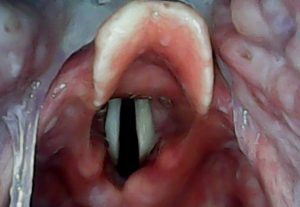

ویدیو لارنگوسکوپ سانیار، ابزاری سبک و قابل حمل، برای مدیریت راه هواییِ بیماران است. این دستگاه، احتمال انتقال آلودگی‌های تنفسی (مثل کرونا) را برای متخصصین، دستیاران آن‌ها و سایر کاربران، کاهش می‌دهد. یکی از مهم‌ترین ویژگی‌های آن، تیغه منحصربفردش است. در واقع این دستگاه، یکی از دغدغه‌های اصلی را برای متخصص برطرف کرده؛ به نحوی که هنگام مواجهه با هر نوع بیمار، دیگر دغدغه انتخاب تیغه مناسب را نخواهد داشت چرا که ویدیو لارنگوسکوپ بزرگسال سانیار، برای کودک 7-8 ساله تا بیماران بسیار چاق، و ویدیو لارنگوسکوپ خردسال سانیار نیز، از سنین 14-15 سال تا نوزادان نارس، به سادگی قابل استفاده است. در واقع، مشکلات لیزخوردن زبان بیمار از روی تیغه و لوله گذاریِ بیمارانِ دیفیکالت (سخت)، با طراحی سه قوسیِ تیغه، برطرف شده است.